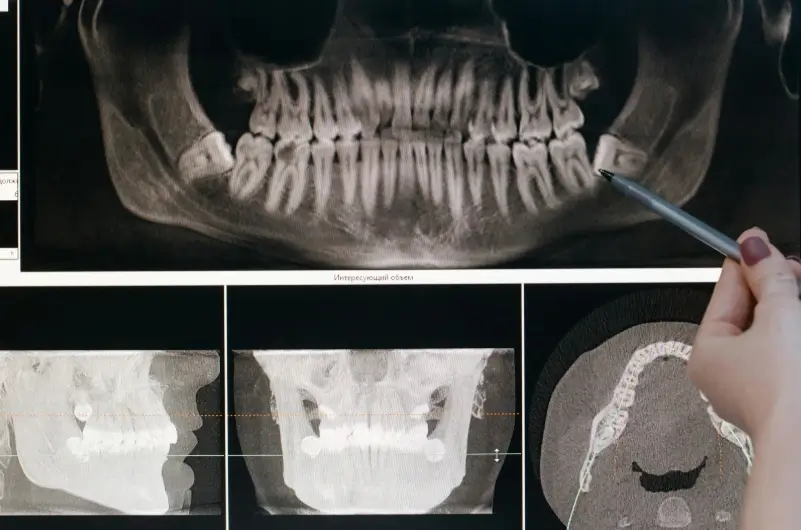

- ปรึกษาทันตแพทย์และ X-ray: เพื่อดูตำแหน่งและความยากง่ายของการผ่าฟันคุด

ไม่จำเป็น ทันตแพทย์สามารถมองเห็นตำแหน่งและทิศทางของฟันคุดได้จากภาพ X-ray ตั้งแต่ฟันยังฝังตัวอยู่ใต้เหงือก การผ่าตัดในขณะที่รากฟันยังเจริญไม่เต็มที่ช่วงวัยรุ่น มักจะทำได้ง่ายและฟื้นตัวเร็วกว่าการรอจนเริ่มปวดฟันคุด